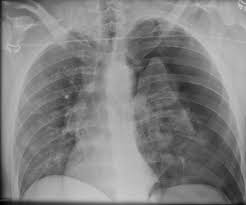

Pneumothorax Symptoms | The most common pneumothorax symptoms are:56. Spontaneous pneumothorax associated with ankylosis spondylitis // rheumatol. Read more about symptoms, diagnosis, treatment, complications, causes and prognosis. Pneumothorax is a painful condition of the lung, commonly referred to as a collapsed lung. Pneumothorax of the chest is easy to suspect without instrumental examination.

The main causes of symptomatic pneumothorax: A small pneumothorax may even go unnoticed. The most common pneumothorax symptoms are:56. Pneumothorax is a painful condition of the lung, commonly referred to as a collapsed lung. Pneumothorax of the chest is easy to suspect without instrumental examination.

In the initial stages of pneumothorax, symptoms may not be very prominent. Pneumothorax symptoms comprise of difficulty in breathing and loss of lung function. Dr jeremy jones ◉ et al. Test characteristics of ultrasonography for the detection of pneumothorax: Webmd explains how a collapsed lung can happen in people who are otherwise healthy and in people. A small pneumothorax may even go unnoticed. Symptoms normally come on almost immediately and commonly begin with chest pain. Pleural aspergillosis in a patient with recurrent spontaneous pneumothorax. Pneumothorax refers to a condition in which there is air in the pleural cavity. Learn what a pneumothorax is, the different types, the symptoms, how to diagnose it, and the treatment in this episode of quick & ez. The main symptoms of a pneumothorax are sudden chest pain and shortness of breath. Pneumothorax is a painful condition of the lung, commonly referred to as a collapsed lung. What are the symptoms of pneumothorax?

Pneumothorax of the chest is easy to suspect without instrumental examination. Also known as pneumothorax, collapsed lung is a rare condition that may cause chest pain and make it hard to breathe. Pleural aspergillosis in a patient with recurrent spontaneous pneumothorax. Pneumothorax (collapsed lung) is an injury to the lung that causes air or gas to build up in the thin layer of tissue that covers the lungs and pneumothorax can lead to a collapsed or punctured lung. The most common pneumothorax symptoms are:56. Some develop as a complication from a chest. Learn what a pneumothorax is, the different types, the symptoms, how to diagnose it, and the treatment in this episode of quick & ez. People with more severe symptoms of a pneumothorax, such as substantial shortness of breath, require emergency treatment in a hospital. Most cases occur 'out of the blue' in healthy young men. Knowledge of the symptoms of the condition will help to promptly seek qualified help and the preservation of human life. Guidelines for the diagnosis and treatment of spontaneous pneumothorax. A pneumothorax is an abnormal collection of air in the pleural space between the lung and the chest wall. A pneumothorax is air that is trapped next to a lung.

Spontaneous pneumothorax associated with ankylosis spondylitis // rheumatol. In the initial stages of pneumothorax, symptoms may not be very prominent. Pulmonary tuberculosis (a breakthrough into the it should be pointed out that the physical symptoms of pneumothorax with a small accumulation of air. Symptoms normally come on almost immediately and commonly begin with chest pain. 16 alrajhi k., woo m.y., vaillancourt c. Abreu, i., guedes, m., duro, r., lopes, s., maciel, j., santos, l. A pneumothorax is an abnormal collection of air in the pleural space between the lung and the chest wall. Symptoms of pneumothorax may develop during rest, sleep, or while awake, or as a result of sudden trauma such as a chest wound. Knowledge of the symptoms of the condition will help to promptly seek qualified help and the preservation of human life. Pneumothorax refers to a condition in which there is air in the pleural cavity. Some develop as a complication from a chest. Symptoms include chest pain and trouble breathing. Webmd explains how a collapsed lung can happen in people who are otherwise healthy and in people.